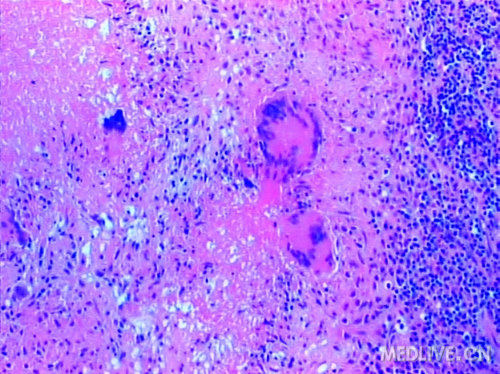

典型的结核结节,中央有多少不等的干酪样坏死,外面围绕着上皮样细胞。可见朗罕氏多核巨细胞。外围大量的淋巴细胞